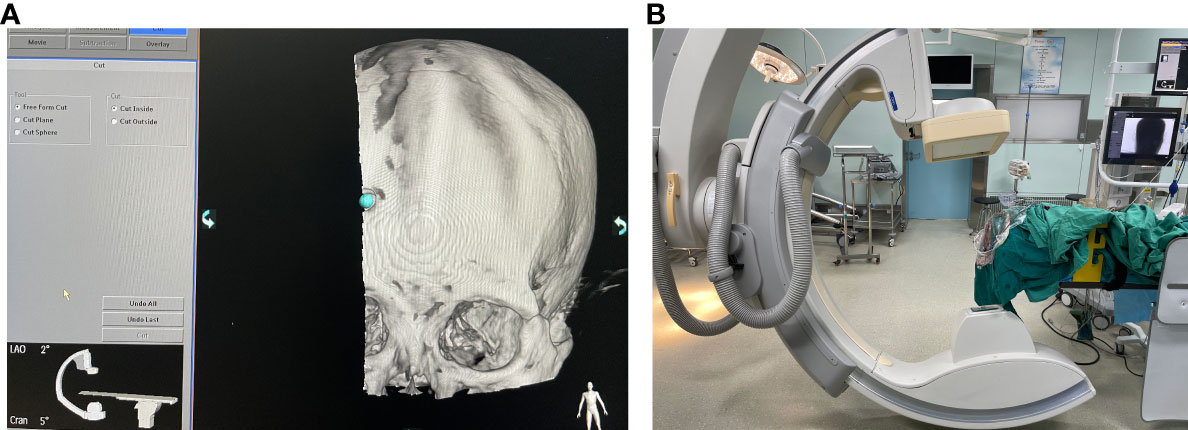

The surgical incision site was marked with a metal object on the forehead, approximately 2 cm from the midline and 3 cm from the orbit on the hematoma side (Figure 2). The priority was to make an incision in the frontal stria and avoid the frontal sinus to prevent cerebrospinal fluid leakage after surgery and ensure an aesthetically pleasing appearance after wound healing. A hole was drilled in the bone at the metal mark (Figure 3). The C-arm CT function of the digital subtraction angiography (DSA) machine was used to collect the original data for processing; display the coronal, sagittal, and axial CT images; mark the center of the hematoma; and set it as the target site for the puncture (Figure 4). The 3D reconstruction of brain tissue was performed using the 3D reconstruction software Xper CT of the DSA machine, and the bone hole displayed in gray scale was adjusted as the puncture point. Subsequently, the 3D stereo image was rotated, overlapping the puncture point and puncture target. The laser emission direction was determined using the principle of “two points and one line,” and the real-time 3D reference image working angle was recorded (Figure 5). The skull was cut along the coinciding point, and the distance between the puncture point and the puncture target was measured as the puncture depth (Figure 6).

2.4.2 DSA machine panel operation

The 3D APC function was used in the Xper APC automatic position control module to automatically position the rack movement to the angle displayed by the 3D reference image (Figure 7) (9).

2.4.3 Surgical procedure

A surgical incision was planned on the forehead scalp at the metal marker, with a length of approximately 2 cm. We stuck the bottom of the laser emitter on the FD plate, making the laser emitted from it perpendicular to the FD plate, then moved the laser emitter, and focused the cross-laser on the puncture point. Consequently, the direction of laser emission passed through the puncture point and puncture target simultaneously, which was determined as the puncture direction, and the puncture needle was held at the puncture point to conduct the puncture. During puncture, the laser focus was continuously placed at the center of the needle tail. At this time, the puncture of the trocar was continuously directed toward the center of the hematoma. Puncture depth was defined as the distance from the puncture point to the puncture target measured before surgery (Figure 8). Dark red blood flowed out through the drainage tube after the tube core was pulled out.